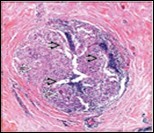

Core needle biopsy of idiopathic granulomatous mastitis enunciates multiple aggregates of non- caseating epitheloid cell granulomas within and encompassing breast lobules, constituted of epitheloid histiocytes, lymphocytes, neutrophils and multinucleated giant cells. Granulomatous inflammation is predominantly lobulo-centric. The inflammation is preponderantly composed of lymphocytes, plasma cells, epitheloid histiocytes, multinucleated giant cells and neutrophils. Neutrophils can configure micro-abscesses and encompass vacant micro-cystic cavities, morphological features which are in common with cystic neutrophilic granulomatous mastitis. Non specific lobulitis along with a lymphoid and plasma cell infiltrate accompanies the granulomatous inflammation. Necrosis is usually absent. Neutrophilic micro-abscesses can be accompanied by fistula formation 4, 5.

Multinucleated giant cells are detected in an estimated three fourths (78.5%) instances. Plasma cells are discernible in around half (53.9%) of the subjects and usually appear at the margins of cystic vacuoles with centric accumulation of neutrophils within the granulomas.

Figure 3.Granulomatous mastitis with scattered langhans and foreign body giant cells, epitheloid cell granuloma and lymphoid ingress11.

Figure 4.Granulomatous mastitis with epitheloid cell granuloma, langhans and foreign body giant cells with lymphocytic rimming12.

Figure 5.Granulomatous mastitis with disseminated epitheloid cell granuloma, langhans giant cells, lymphocytic and plasma cell dispersal13.

Figure 6.Granulomatous mastitis with numerous epitheloid cell granuloma, foreign body giant cells and a peripheral rimming with lymphocytes14.